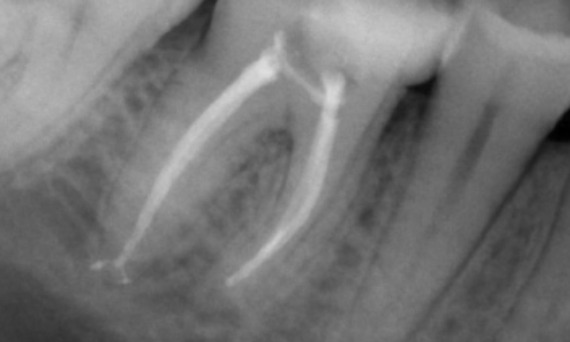

Après : TruNatomy a été choisi dans ce cas pour permettre une approche adaptée aux caries et une préservation de la dentine péricervicale, en particulier au niveau de l’aspect mésial où la restauration de la dent était minimale.